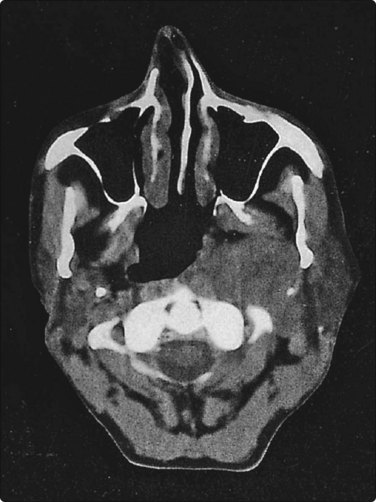

Nasopharyngeal carcinoma (NPC) (Figs 4.8, 4.9, and 5.59)44-47

image

Fig. 4.8 Nasopharyngeal carcinoma (squamous cell carcinoma, WHO type II)

Epithelial fragment of spindly and basaloid squamous epithelial cells with no evidence of keratinization (Pap, HP).